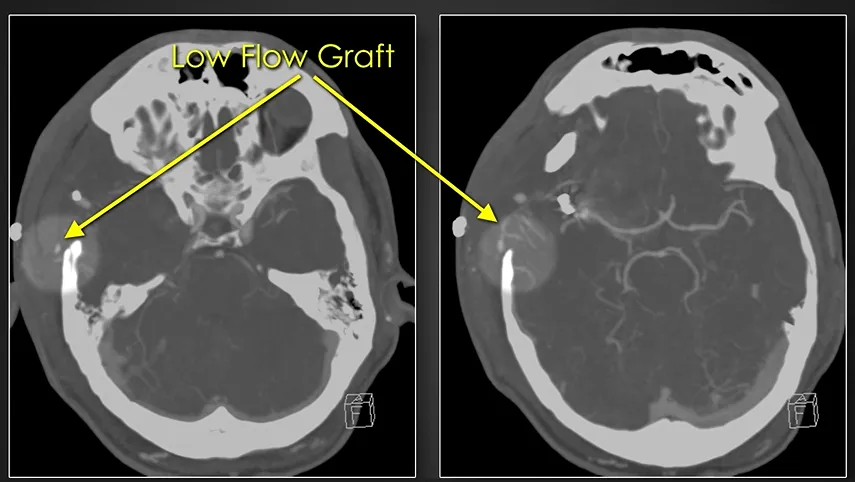

手术实施右额颞开颅,术中注意保护颞浅动脉。完成硬膜外暴露后,于卵圆孔外侧的中颅窝底钻一骨孔。随后解剖外侧裂,分离出其中较粗大的M3分支。通过内镜技术获取大隐静脉移植物,将其一端与颈外动脉进行吻合,另一端则经中颅窝底骨孔形成的隧道穿行,与较粗大的M3分支行端侧吻合。动脉瘤被成功夹闭,受累的较细小M3分支被离断,并与颞浅动脉行端端吻合。术中吲哚菁绿荧光血管造影证实两处搭桥血管均保持通畅。术后患者接受了规范的抗生素治疗及二尖瓣置换术。

术后影像